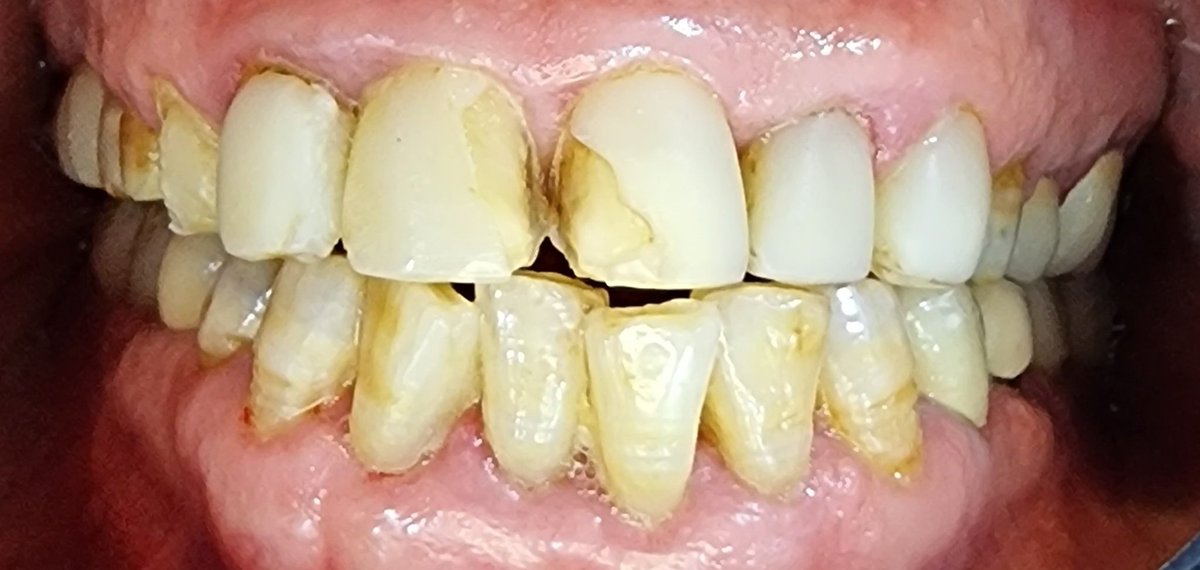

كما نوهت كثيرا ومرار وتكرارا يوميا تجي حالات معموله بالاخص فينير وتلبيسات وعندما يتم فحص السن يكون السن ميت وذكرت اسباب كثره ومتكرره وهي المبالغه في تحضير وحك السن للفينير والتلبيس وهو سن حي ومن غير متخصص وغير فاهم بخطورة هذا العمل وايضا وجود حشوات عميقه بهذا السن وفتحات بالتلبيس

عندما نقول الكتاب باين من عنوانه معاناة المريضه بسقوط الفينير المتكرر مرتين وثلاث في الاسنان العلويه يتضح جليا مدى سوء العمل من بدايته الى نهايته فحص الاسنان كلها غير حيه ومتعفنه وايضا هل هذا يعتبر علاج فينير صحيح لا طبعا ولا تمت للفينير ولا التركيب بأي صله ولا علاقه

سن معمول له عصب ووتد ومعمول له فينير سيئ وليس تركيب ومتكسر وشكل بشع غير لائق بجودة عمل فاااضحه للاسف وغير مقبوله في تخصصنا

ناب تم فحصه ومركب عليه فينير سيئ السن تكلس وبالفحص السن ميت non vital تم فتح التكلس وعلاج العصب وجميع الاسنان الاماميه بهذا الشكل للاسف ان المريض ذكر لي انها بأرقى أرقى عيادات الرياض وهذا ما استغربته واثبت ذلك بالفعل يعني لا احد يقول المريض ملخبط